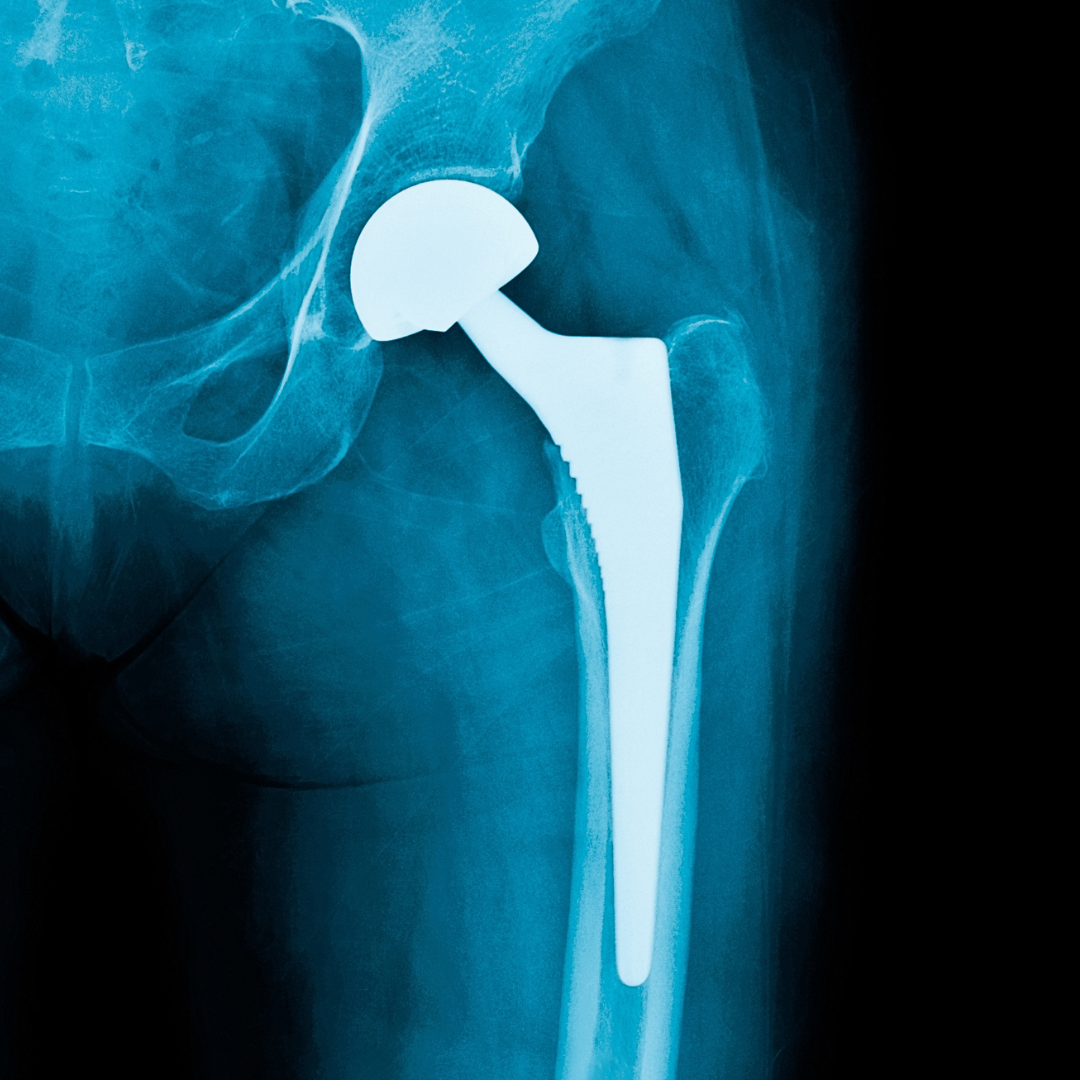

Hip replacement surgery is recommended when conservative treatments such as medication, physiotherapy, or lifestyle modifications fail to relieve pain. Fortunately, with advancements in orthopedic techniques, modern hip replacement has become safer and more effective.

Total Hip Replacement – replacing the damaged hip joint with an artificial implant.

Furthermore, he uses high-quality implants that are durable and designed to provide long-term comfort and mobility.